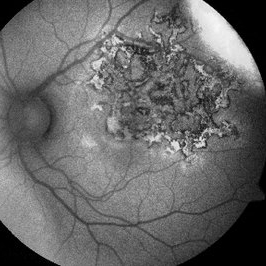

High Risk PDR With Pre Retinal Hemorrhage

A montage of an eye with high risk PDR having pre retinal hemorrhage. Florid NVE are noted in the temporal quadrant. peripheral PRP marks are seen .

Photographer: Ashawini Borde

Imaging device: FF 450 Plus IR

Condition/keywords: hemorrhage, neovascularization of the disc (NVD), nonproliferative diabetic retinopathy, proliferative diabetic retinopathy (PDR)